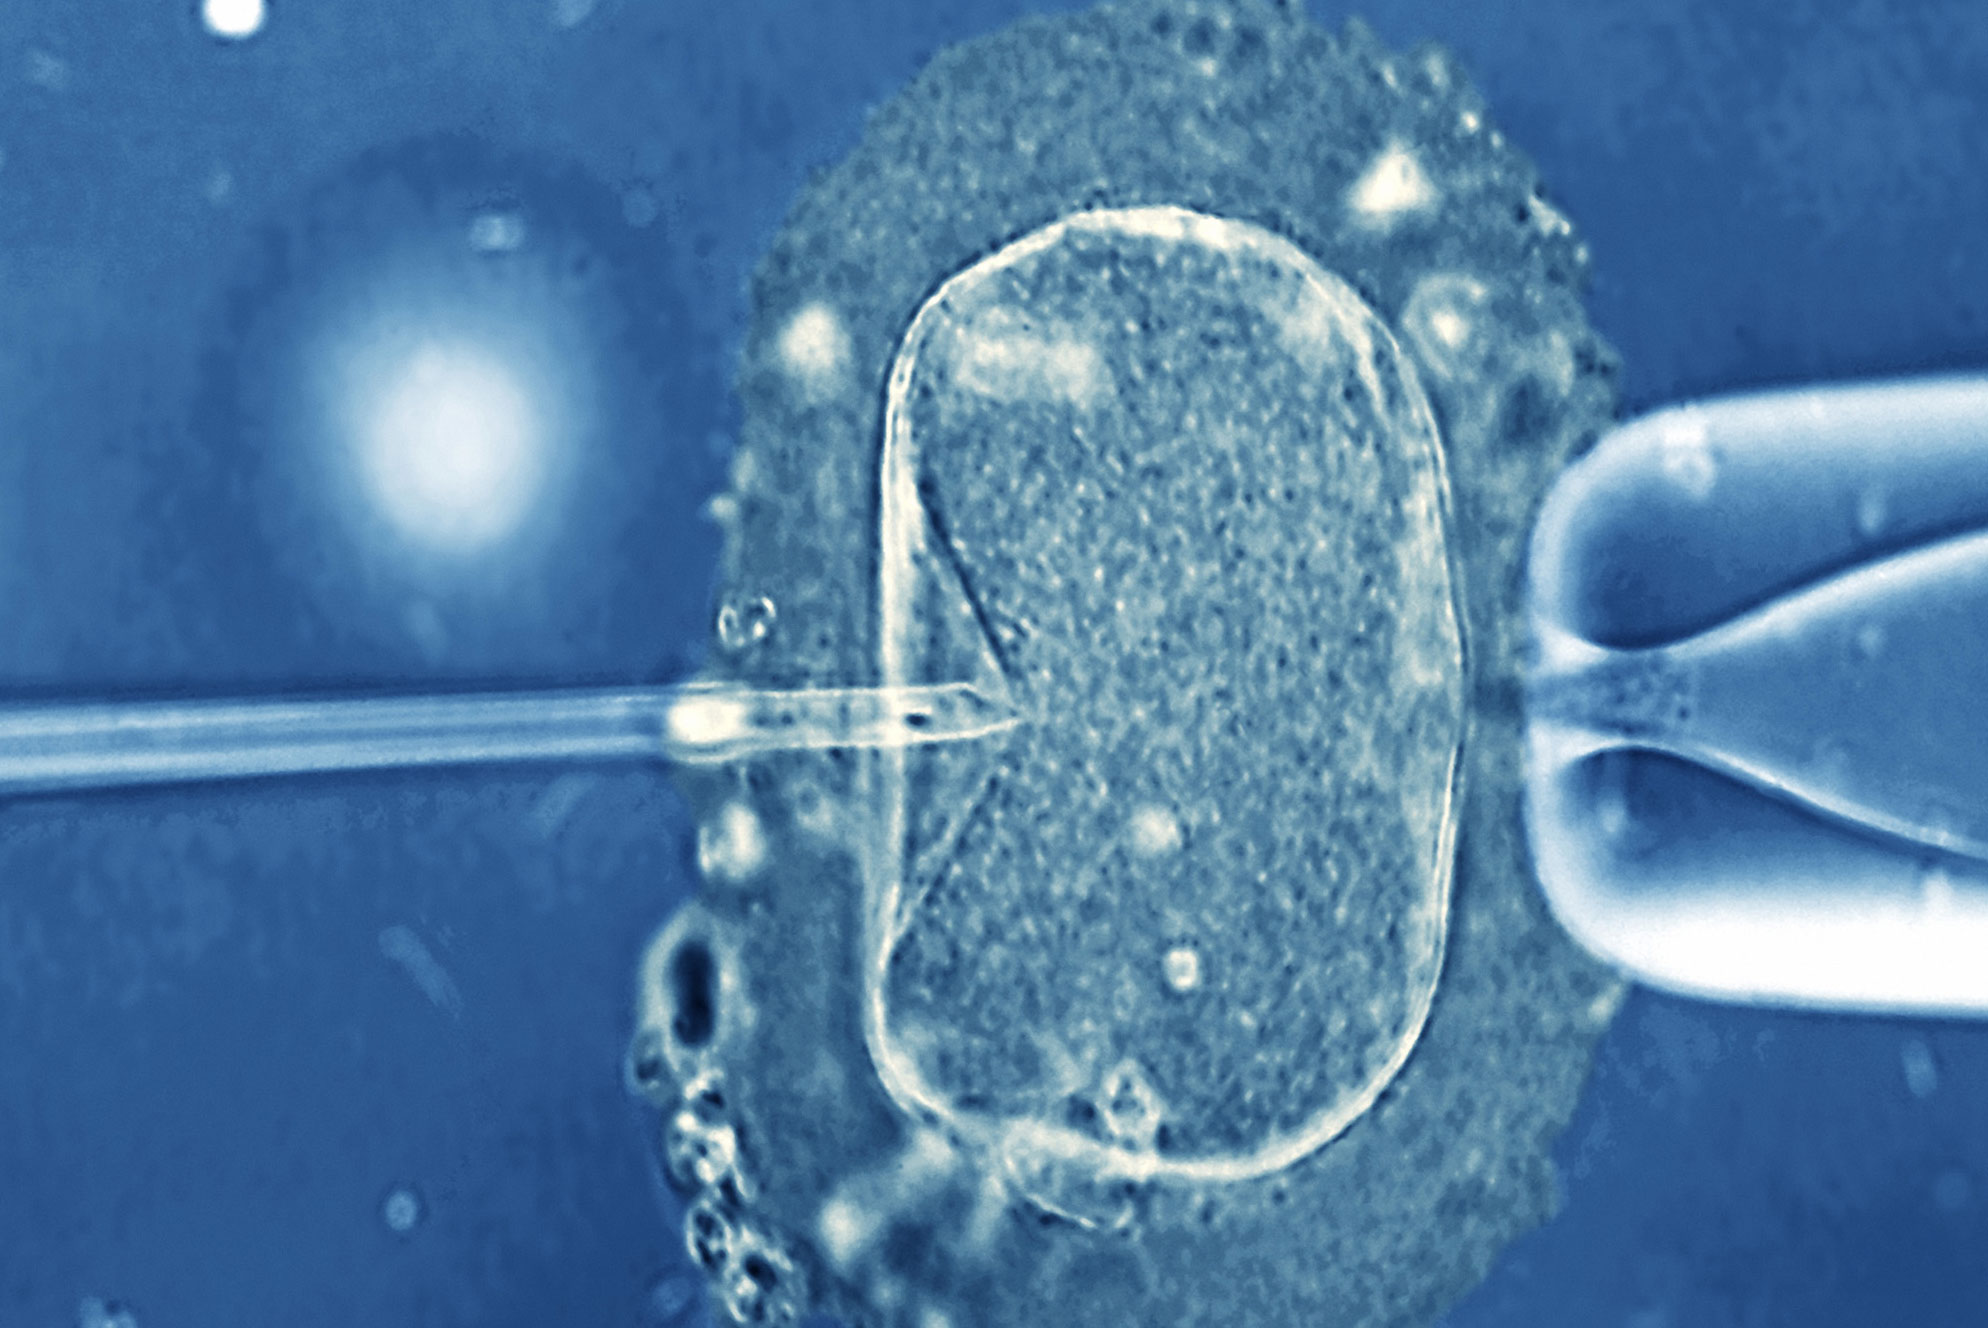

Ο ρόλος των υδατανθράκων για την ομαλή ανάπτυξη του εμβρύου

Μια διατροφή με χαμηλή περιεκτικότητα σε υδατάνθρακες κατά την κύηση ίσως αυξάνει τον κίνδυνο απόκτησης παιδιού με σοβαρές γενετικές ανωμαλίες, σύμφωνα με αμερικανική μελέτη που δημοσιεύεται στο επιστημονικό έντυπο Birth Defects Research.